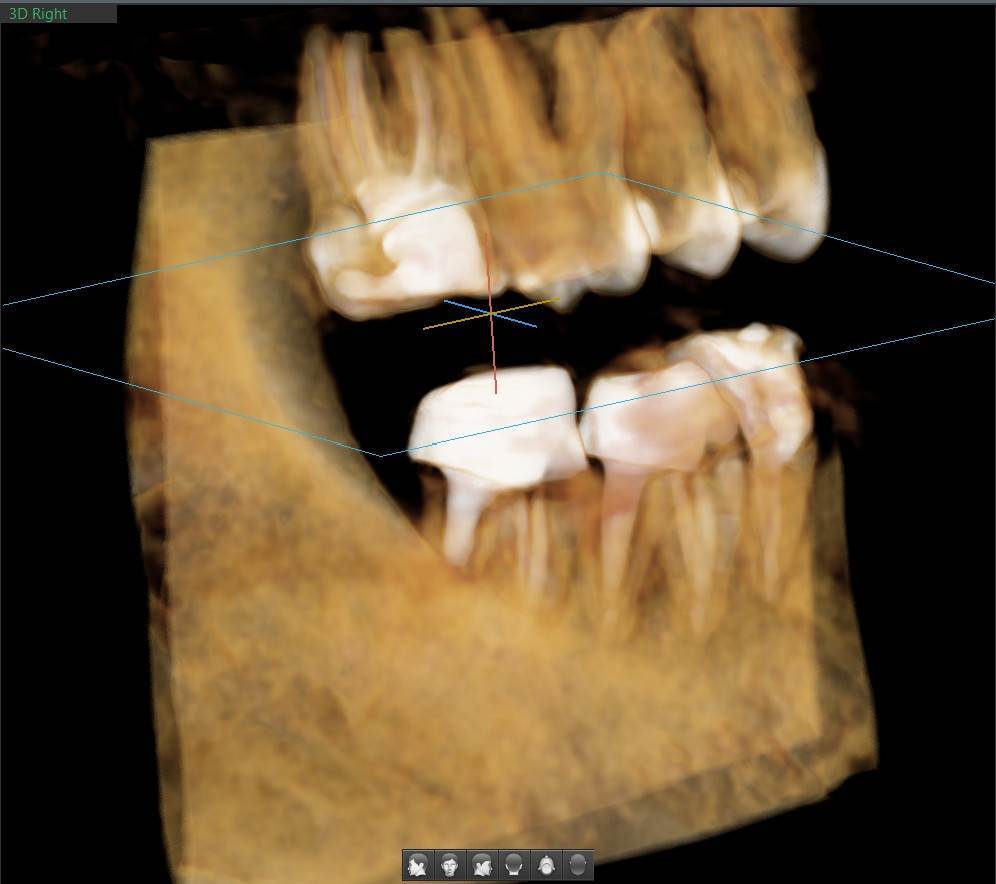

A-V-S Опубликовано 3 марта Поделиться Опубликовано 3 марта Здравствуйте. У меня такая ситуация: В начале января 2026 начал болеть зуб 7ка снизу слева - боль развивалась постепенно - в итоге стало больно жевать. Сделал КТ. Лечащий стоматолог сказал, что это проснулось спящее воспаление, перелечивать каналы зуба сложно - надо сверлить буром и доставать стекловолоконный штифт - надо удалять. В следующие дни открылся свищ и боль ушла. Свищ продолжает быть с периодическим набуханием и сдуванием после выброса гноя белого цвета. Этот зуб лечили с установкой стекловолоконного штифта чуть больше 5 лет назад. Посмотрите, пожалуйста, приложенные снимки и посоветуйте как быть - можно ли перелечить и сохранить зуб ? Ссылка на комментарий

АнтонТЛТ Опубликовано 3 марта Поделиться Опубликовано 3 марта Добрый вечер, лучше выложить несколько срезов этого зуба, либо архив с кт. По представленным снимкам, есть подозрение о наличии трещины между корнями зуба. 1 1 Ссылка на комментарий

Гарриевич Опубликовано 6 марта Поделиться Опубликовано 6 марта Не знаю обрадует Вас это или огорчит, но зуб можно сохранить соседний тоже с воспалением кстати 1 1 Ссылка на комментарий

red_butler Опубликовано 9 марта Поделиться Опубликовано 9 марта В 03.03.2026 в 22:49, A-V-S сказал: можно ли перелечить и сохранить зуб ? можно Ссылка на комментарий

Doc Опубликовано 10 марта Поделиться Опубликовано 10 марта 16 часов назад, A-V-S сказал: на соседнем свища нет. Тоже надо перелечивать вместе с 7 ? Отсутствие свища не снимает проблемы наличия кисты на этом зубе. Рано или поздно будет вам свищ, либо зуб так заболит, что придется удалять безо всякого свища. 1 Ссылка на комментарий